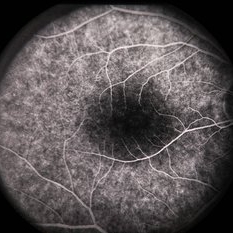

Optic Disc Drusen Autofluorescence

Apr 2 2016 by David Callanan, MD

30-year-old Caucasian male with visual field defect OD > OS.

Condition/keywords: optic disc drusen